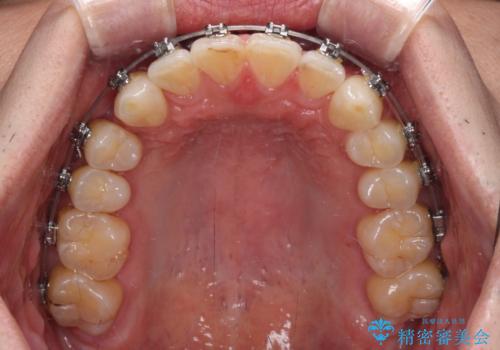

- 以前矯正治療を行ったものの、思い通りの仕上がりではなく、更には後戻りが気になってきたとのことで来院された患者様です。

上顎右側の第一小臼歯が動きにくい歯であり、以前矯正治療を行った際に傾斜した位置のまま終了したことと、それに伴い後戻りで歯列が波打っているようになっていることを大変気にしていらっしゃいました。

咬合平面改善のため、アンカースクリューを多用し、ワイヤー装置にて矯正治療を行うこととしました。